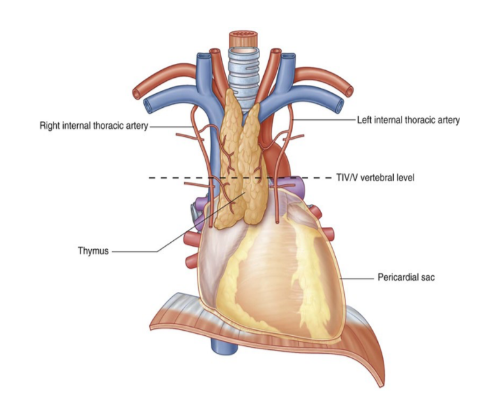

Thymus —

Most anterior component of the superior mediastinum, posterior to the manubrium

Bilobed asymmetrical organ

Upper extent of the thymus can reach into the neck as high as the thyroid gland, lower portion typically extends into anterior mediastinum over the pericardial sac

Begins to atrophy post-puberty

Arteries to the thymus —

Consist of small branches originating from the internal thoracic arteries

Venous drainage —

Usually into the left brachiocephalic vein & possibly into the internal thoracic veins

Superior mediastinum

Major recognizable structures —

Thymus